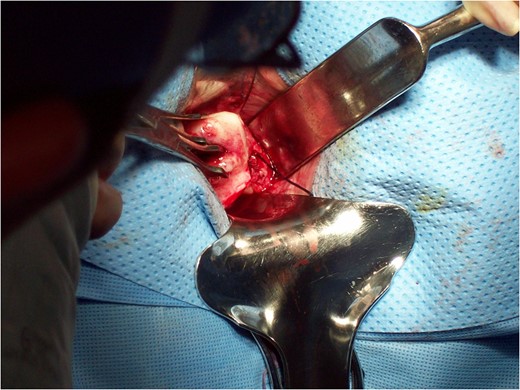

6 and

7). The vaginal cuff was closed by baseball stitches first then with running interlocking stitch of chromic. The cuff was closed from the superior angle to inferior angle and the uterosacral ligaments were approximated to help with vaginal vault support.

Figure 7:

Completion of vaginal hysterectomy.